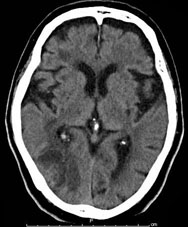

転移性脳腫瘍 肺癌の脳内転移

[ラジオサージャリー前]

CT(左画像): 左下の黒くなっているところが癌、 造影MR(右画像):左下の周りが白い線で囲まれたようになっているところが癌

[ラジオサージャリー後2ヵ月半]

CT、MRともに癌が縮小している。